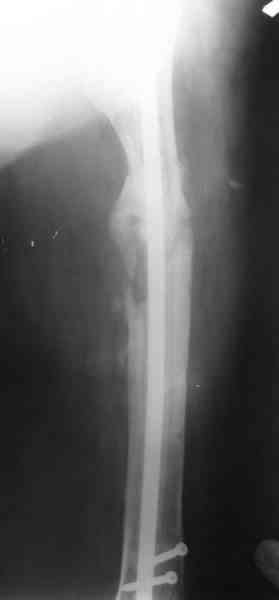

1, 2, 3, 4 - рентгенограммы бедра от 8 августа этого года (через четыре месяца после операции);

4, 5, 6 - рентгенограммы бедра и фотографии пациентки (прошу прощения за низкое качество рентгеновских снимков) от 7 сентября 2007 г.